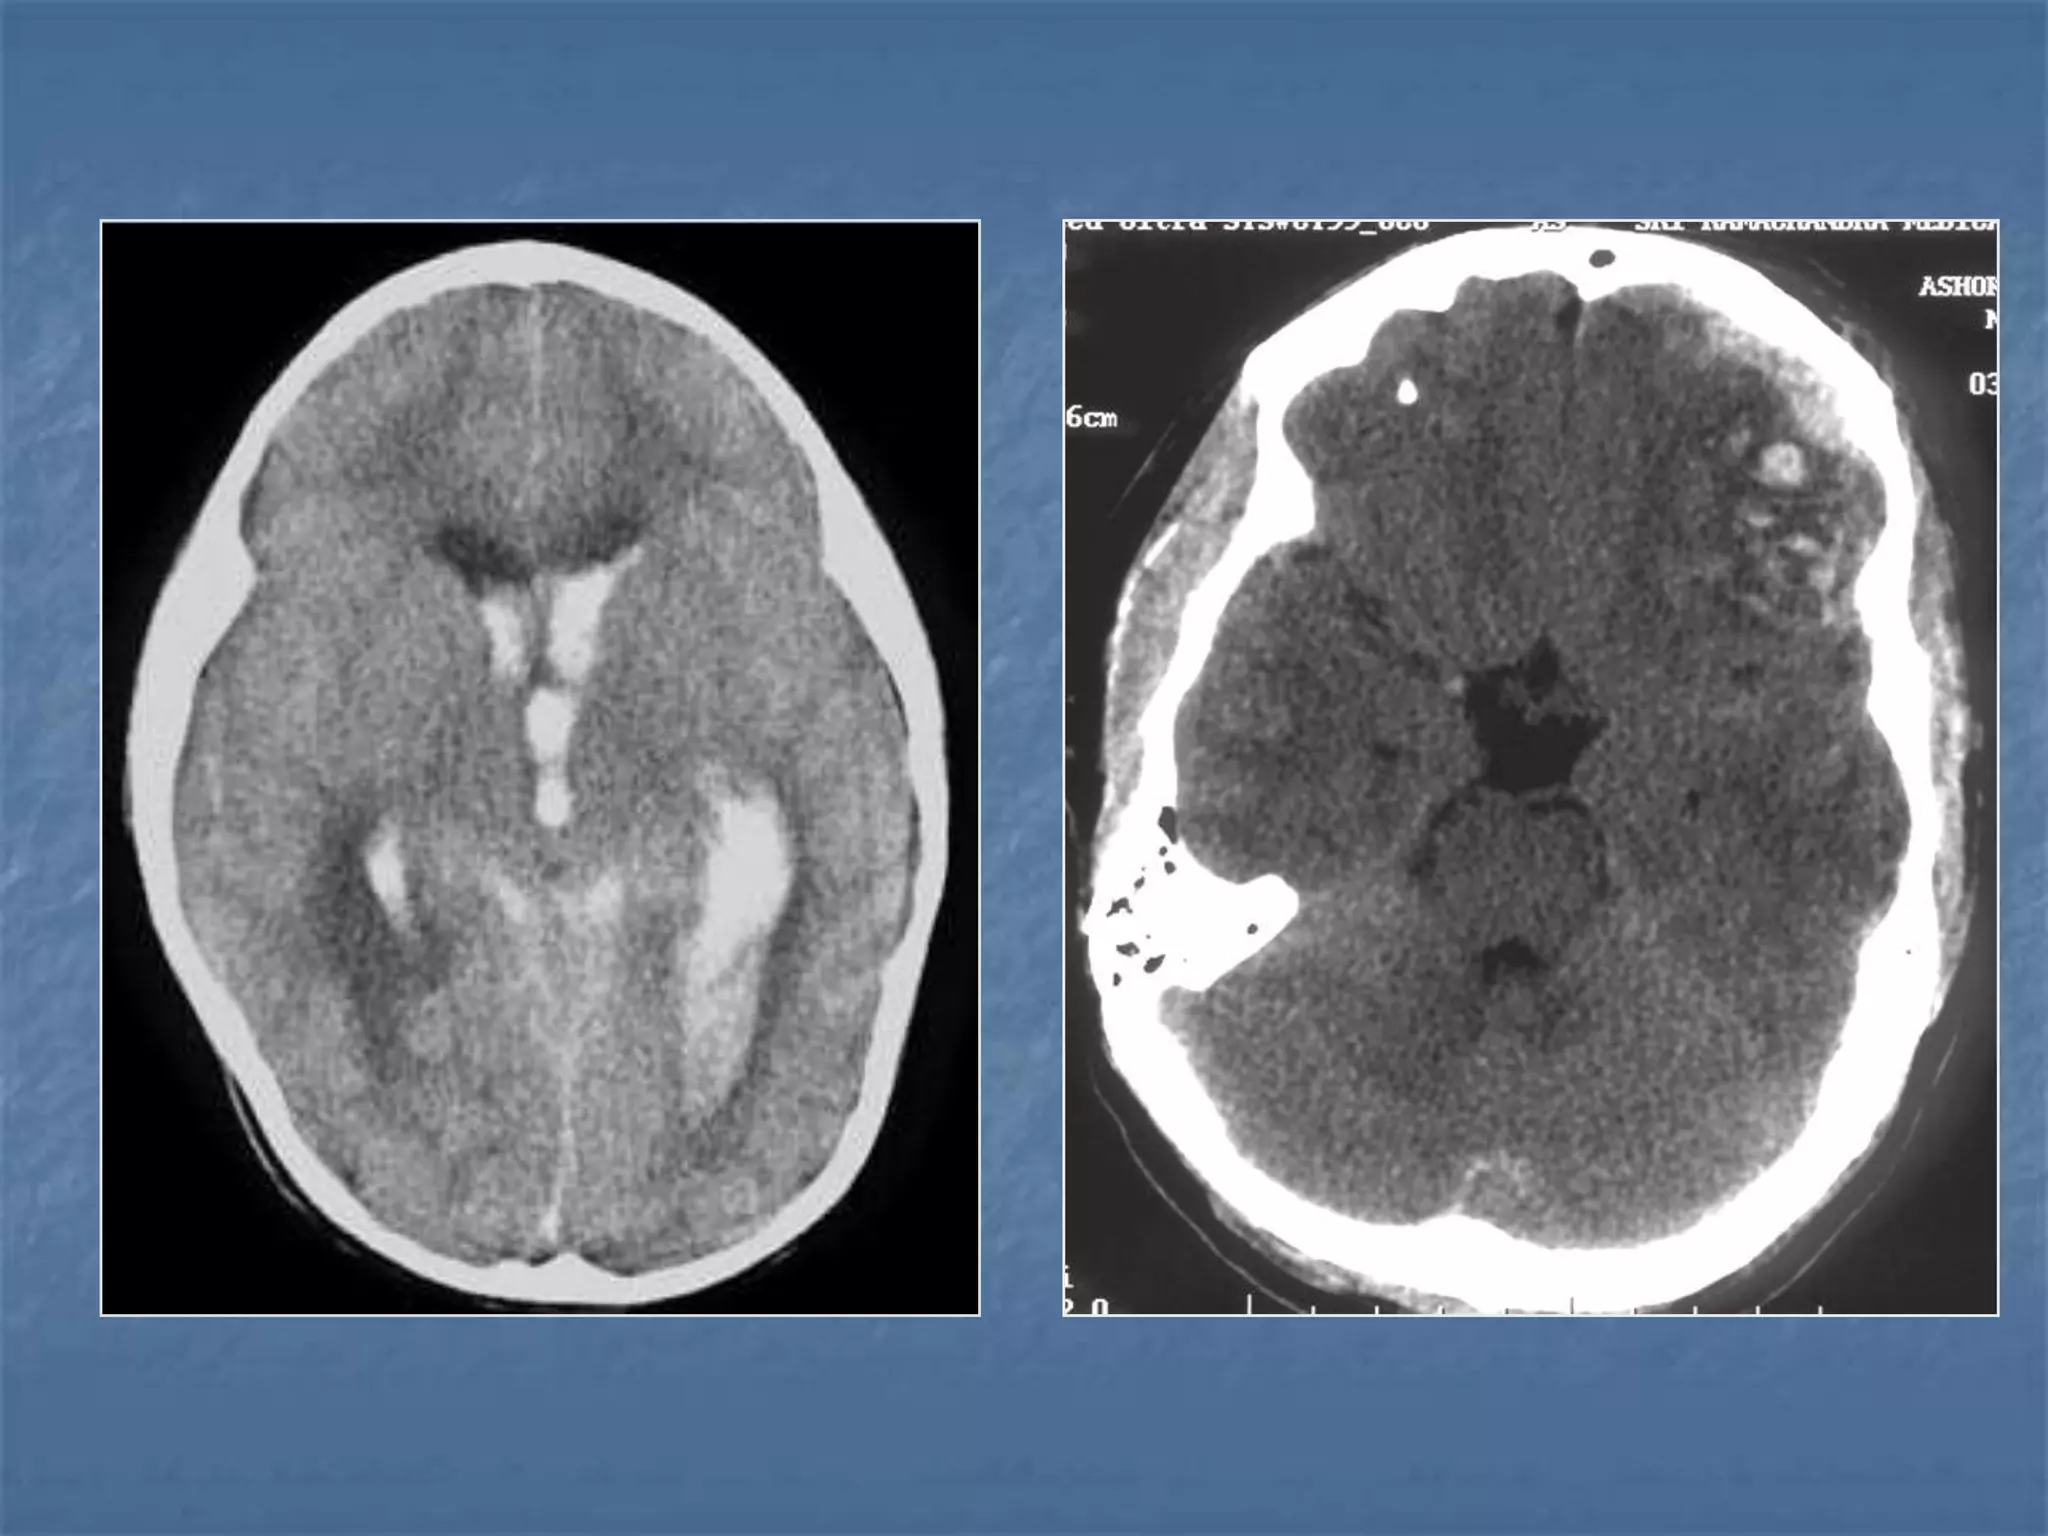

Hypertensive Hemorrhage

 Hypertensive hemorrhage accounts for

approximately 70-90% of non-traumatic primary

intracerebral hemorrhages. It is commonly due to

vasculopathy involving deep penetrating arteries

of the brain. Hypertensive hemorrhage has a

predilection for deep structures including the

thalamus, pons, cerebellum, and basal ganglia,

particularly the putamen and external capsule.

Thus, it often appears as a high-density

hemorrhage in the region of the basal ganglia.

Blood may extend into the ventricular system.

Intraventricular extension of the hematoma is

associated with a poor prognosis.

Haemorrhagic StrokeEtiology

 Hypertension

 Vascular malformation

 Aneurysm

 Trauma

 Amyloid angiopathy

 Tumor

 Coagulopathy

 Hemorrhages can occur in the intraparenchymal,

subarachnoid, intraventricular, subdural and

extradural spaces.

 Location of hypertensive hemorrhage:

Putamen, external capsule, thalamus, pons,

cerebellum, subcortical white matter

Subarachnoid hemorrhage

 In the absence of trauma, the most common cause

of subarachnoid hemorrhage is a ruptured cerebral

aneurysm. Cerebral aneurysms tend to occur at

branch points of intracranial vessels and thus are

frequently located around the Circle of Willis.

Common aneurysm locations include the anterior

and posterior communicating arteries, the middle

cerebral artery bifurcation and the tip of the basilar

artery. Subarachnoid hemorrhage typically presents

as the "worst headache of life" for the patient.

Detection of a subarachnoid hemorrhage is crucial

because the rehemorrhage rate of ruptured

aneurysms is high and rehemorrhage is often fatal.

 CT is currently the imaging modality of choice because

of its high sensitivity for the detection of subarachnoid

hemorrhage. CT is most sensitive for acute

subarachnoid hemorrhage. After a period of days to

weeks CT becomes much less sensitive as blood is

resorbed from the CSF. If there is a strong clinical

indication, LP may be warranted despite a negative CT

since small bleeds can be unapparent on imaging.

On CT, a subarachnoid hemorrhage appears as high

density within sulci and cisterns. The insular regions

and basilar cisterns should be carefully scrutinized for

subtle signs of subarachnoid hemorrhage.

Subarachnoid hemorrhage may have associated

intraventricular hemorrhage and hydrocephalus.